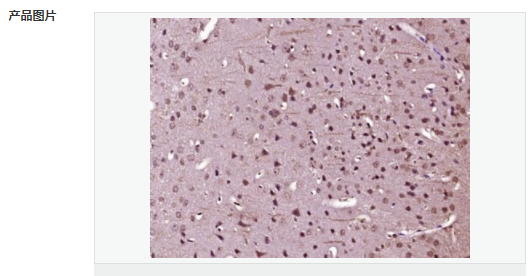

產(chǎn)品應用ELISA=1:5000-10000 IHC-P=1:100-500 (石蠟切片需做抗原修復)

image.png